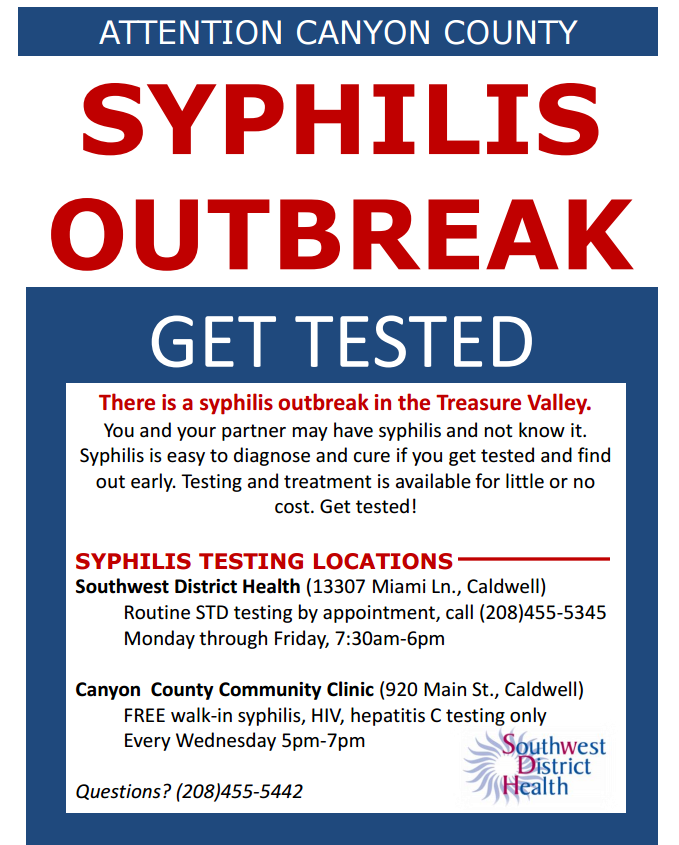

Idaho: Syphilis outbreak in Canyon County – Outbreak News Today